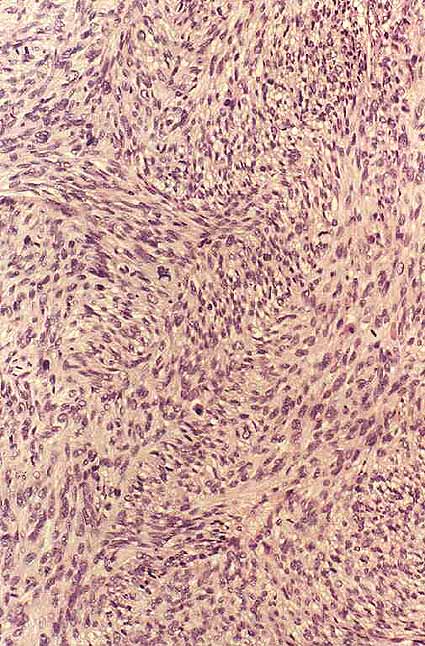

Fig 3: proliferación fusocelular. Patrón de crecimiento fascicular (200x, HE)

Fig 1: nucleos elongados, con atipía y frecuentes mitosis (400x, HE)